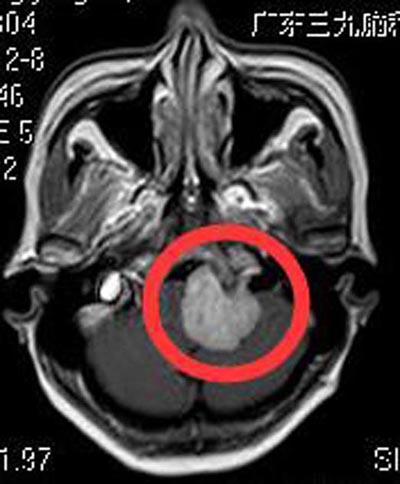

47岁的徐女士一个月前出现左侧肢体麻木乏力,偶有头晕,无明显头痛、耳鸣等不适,担心是“脑中风”,立即在当地医院行头颅检查,提示:左侧桥小脑角占位。广东三九脑科医院神经头颅MR检查显示:左侧桥延前池占位性病变,大小约3.2cm×2.6cm×3.2cm,考虑脑膜瘤。

▲手术前